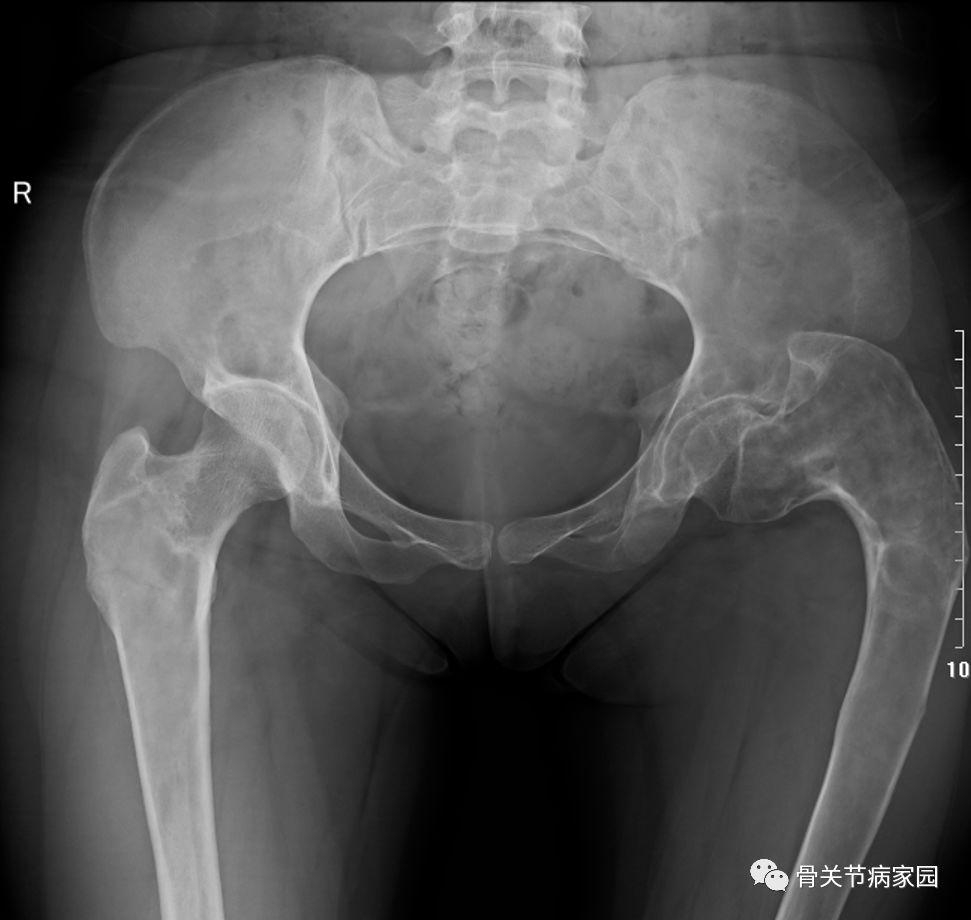

牧羊人手杖 畸形女孩的求医故事 骨关节病家园 微信公众号文章阅读 Wemp